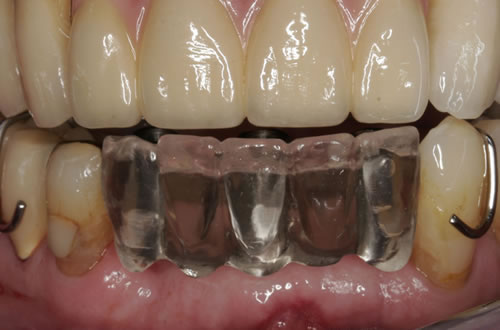

3.4 Reduzierte Bezahnung

Wenn viele Zähne fehlen und nur noch einige erhaltungswürdige Zähne vorhanden sind, die in den neuen Zahnersatz mit einbezogen werden können, dann spricht man von einer reduzierten Bezahnung. Die prothetische Versorgung wird als Hybridkonstruktion bezeichnet, da sie sowohl auf natürlichen Zähnen als auch auf Implantaten befestigt wird. Die Versorgung kann sowohl festsitzend - verschraubt oder zementiert - gestaltet werden (Abb. 3.24, 3.25), aber auch herausnehmbar, wobei dann häufig teleskopierende Konzepte verwendet werden (Abb. 3.26, 3.27).

Abb. 3.26: Hybridversorgung einer reduzierten Oberkieferbezahnung auf 4 Zähnen und 3 Implantaten.

Abb. 3.27: Ansicht des gaumenfreien, herausnehmbaren Zahnersatzes.